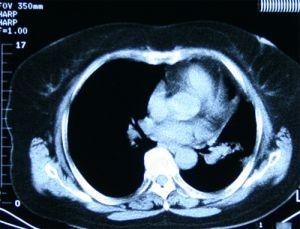

3.CT检查及磁共振检查: 可以揭示下腔静肿物的位置,大小,阻塞范围,以及肿物的性质。

超声动图,部B型超声检查,CT检查,磁共振检查,下腔静房造影等检查对于明确本病的诊断,确立肿扩展的范围,肿大小和环障碍程度的估价,以及手术式的选择具有决定性意义。

3.超声:CT及磁共振检查,或造影检查提示右侧腔和下腔静有肿物或占位病变。